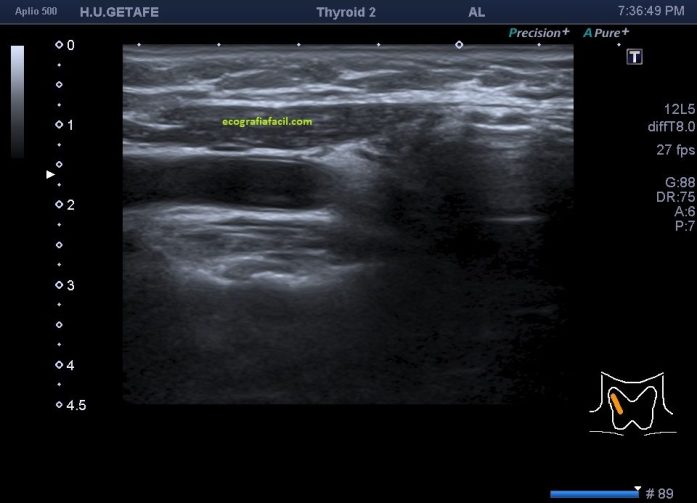

En la imagen 3 y 4 te muestro el desarrollo del estudio normal en esta mujer de 63 años que no tenía ni idea de la ausencia congénita del lado derecho de su tiroides, representado en el corte longitudinal con la imagen 5 donde encontramos «nada» donde debería estar una ecoarquitectura similar a la imagen 4.

Siempre que encontremos una ausencia quirúrgica tiroidea es recomendable reflejarlo en el estudio como hemitiroidectomía o como tiroidectomía según corresponda.